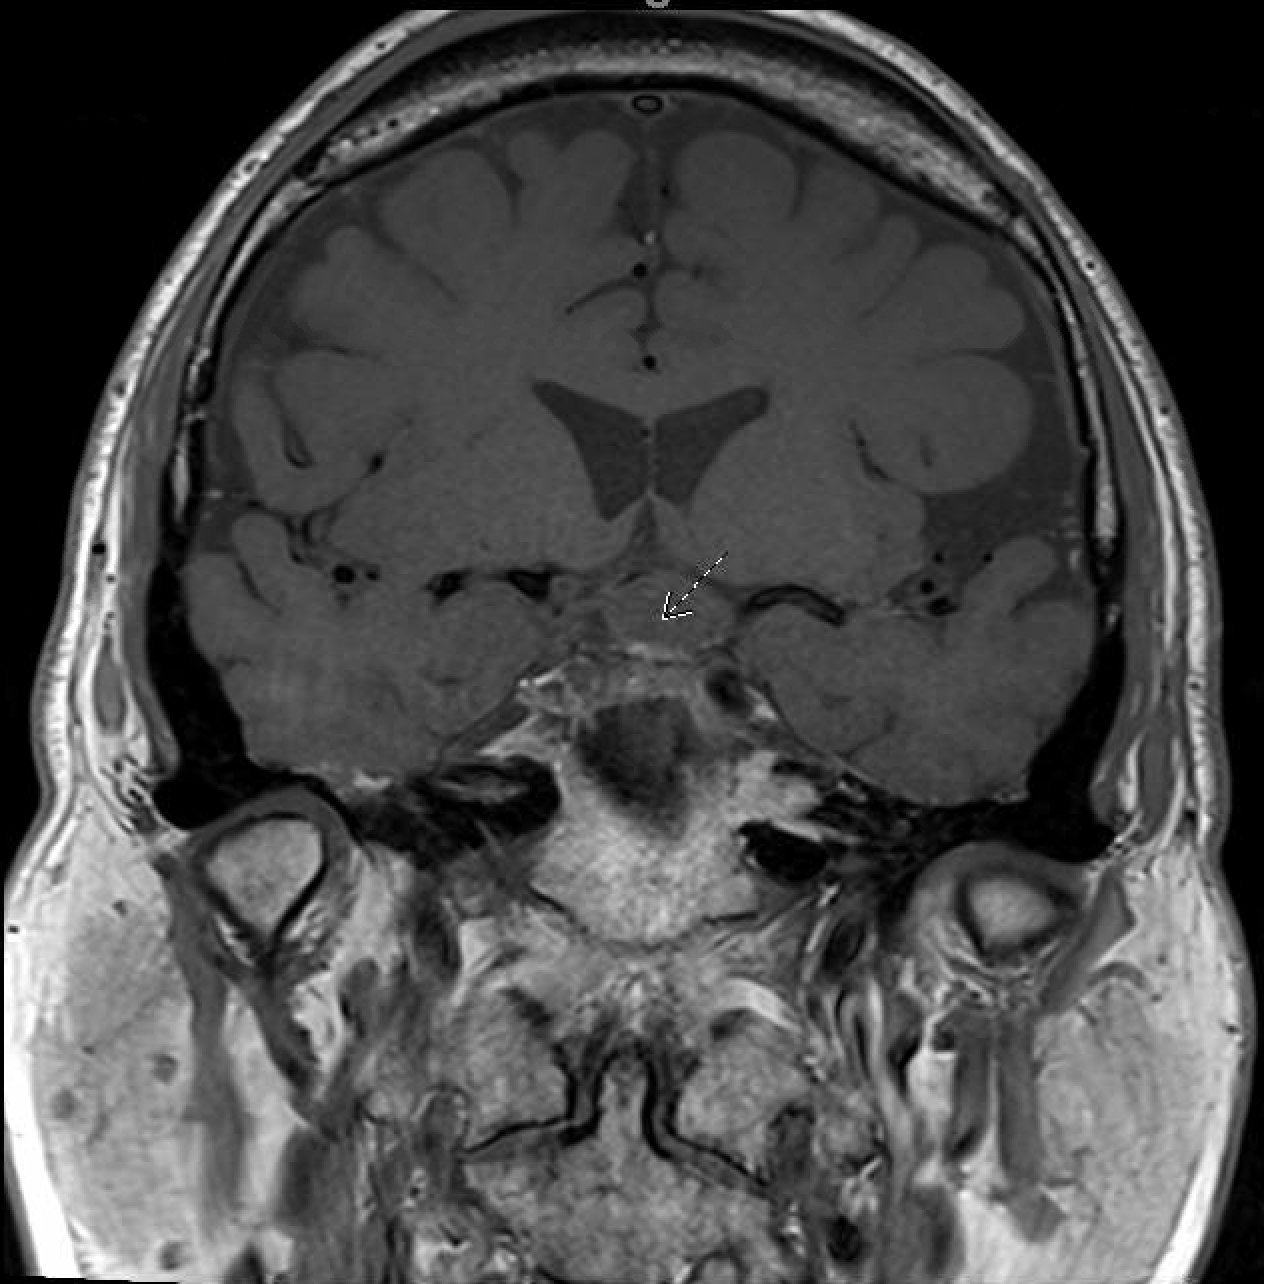

In August 2022, the patient presented again with visual deficits. Repeat MRI showed a 10.3 mm × 14.6 mm × 17 mm cystic mass in the suprasellar area with enhancing mural nodules, most likely related to craniopharyngioma that is causing mass effect on the optic chiasma (Figures 1, 2). He underwent an endoscopic endonasal transplanum transtuberculum approach to the middle fossa skull base with a resection of the middle cranial fossa skull base tumor. Pathology revealed papillary craniopharyngioma, CNS WHO grade 1. BRAF V600E mutation was identified. Subsequently, a CSF leak was present, and he underwent a CSF leak repair. He followed up with the surgical team who monitored for symptoms of clinical relapse. Importantly, the patient never went for radiation.

Figure 2

MRI coronal-transinfundibular showing a cystic mass (white arrow) in the suprasellar area with enhancing mural nodules, most likely related to craniopharyngioma, causing mass effect on the optic chiasma.